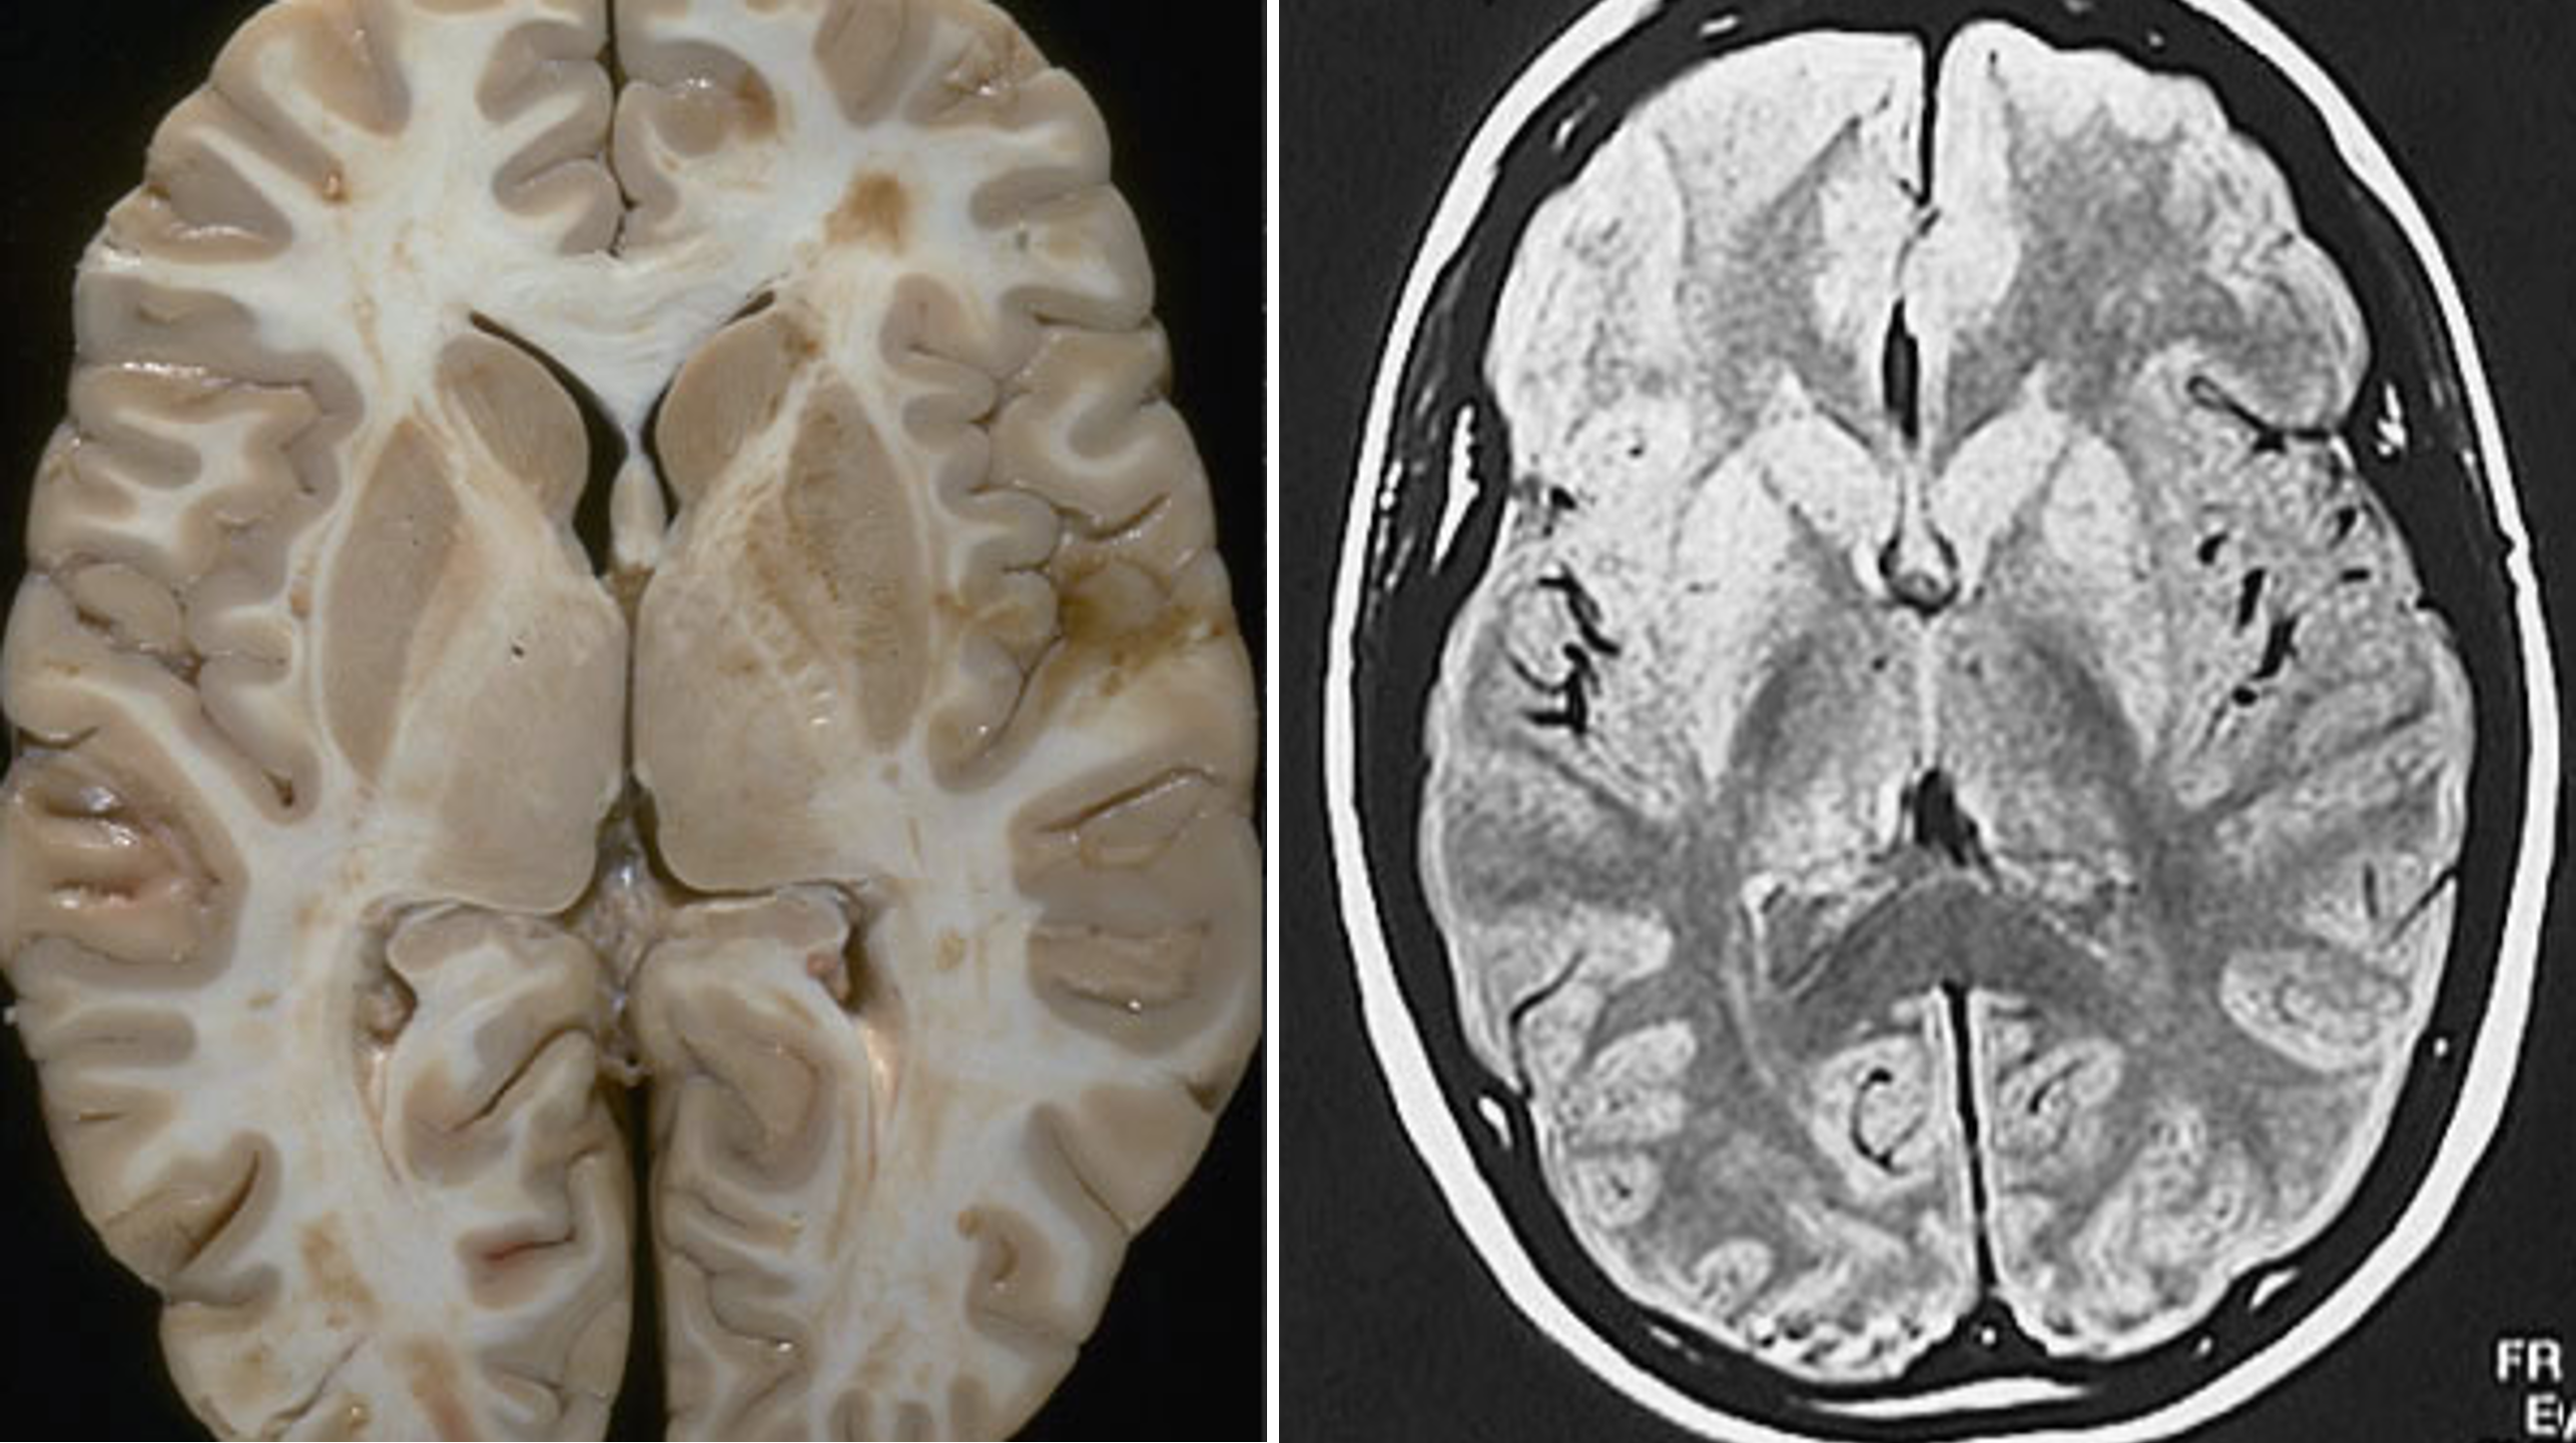

the basal ganglia are large structures that are easily identified in structural MRI scans

The caudate, putamen, and nucleus accumbens have identical cell types and perform similar computations, but receive inputs from different cortical regions. In primates, the separation between caudate and putamen is due to fibers growing between the cortex and thalamus during embryological development. These nuclei are not separated in rats.

the mid-level basal ganglia looks like this

includes:

caudate

ventroanterior thalamus

globus pallidus

putamen

amygdala

Images of the brain from a patient with Huntington’s disease reveals enlarged ventricles and shrunken caudate and putamen nuclei bilaterally.